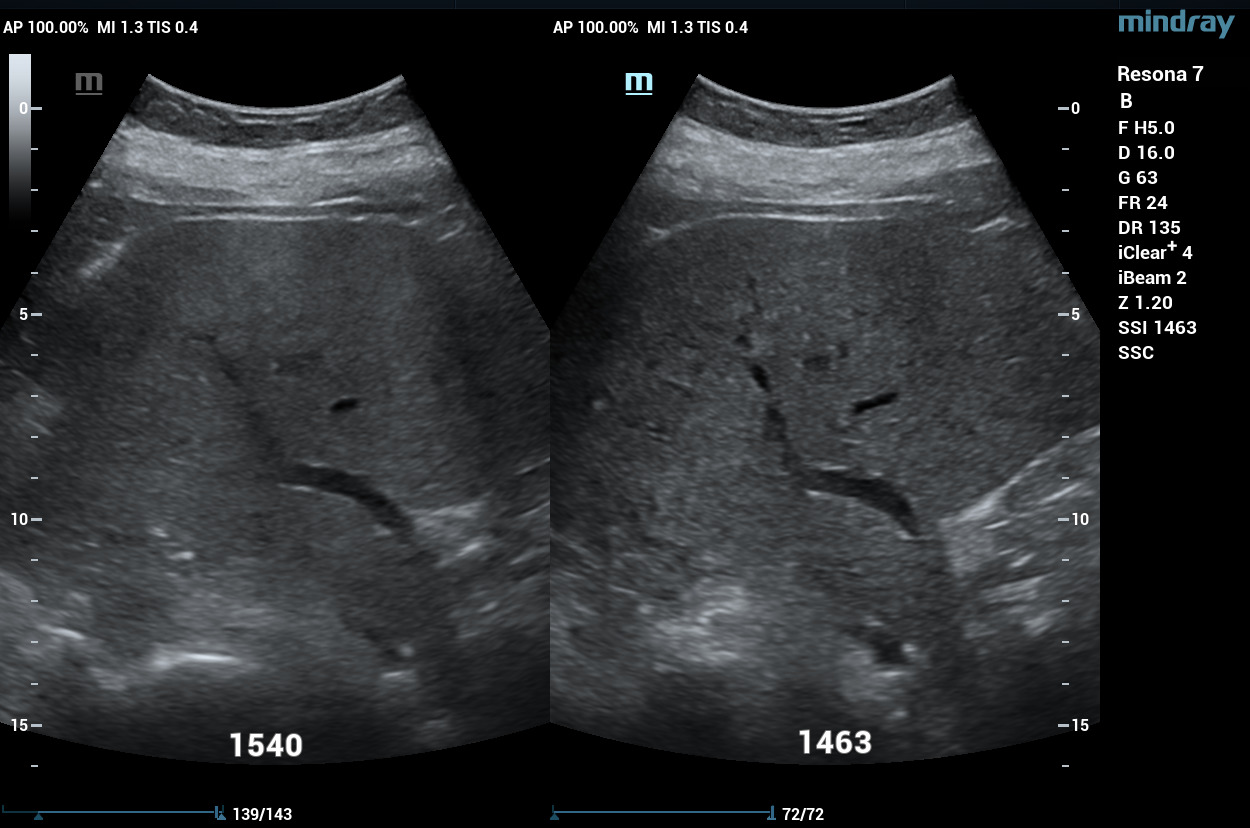

Sound Speed Compensation

Another unique and patented engineering breakthrough that differentiates ZST from traditional hardware-based beamforming platforms is automated digital Sound Speed Compensation (SSC). Historically, ultrasound imaging systems have been calibrated to the inaccurate assumption that ultrasound propagates through all human soft tissue at a velocity of 1,540 meters per second. In fact, many factors affect the actual speed of sound in a particular tissue and failure to compensate for these differences diminishes and limits spatial and contrast resolution in conventional ultrasound systems. At the touch of a button, SSC automatically samples the tissue being examined and recalibrates the software to reflect its specific speed of sound. The resulting enhancements in image quality provide another powerful clinical tool that increases diagnostic confidence, especially when examining diseased organs and structures at deeper depths.

Compare and the difference is clear. Enhanced spatial resolution in a tissue-equivalent pin phantom without Sound Speed Compensation (A) and with Sound Speed Compensation (B).